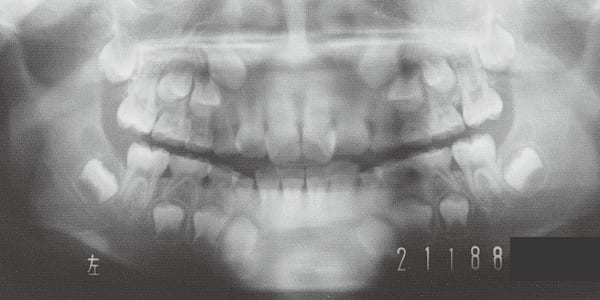

4 Initial Visit 2-11-’88

The Class II condition is pronounced, with a significant overjet of 12.5 mm(3). Although the teeth size are large, crowding is relatively mild. The maxillofacial structure has good depth and a robust bone framework(5). The mandible itself is solid , robust gonial angle, but there is significant anterior-posterior displacement relative to the maxilla(ANB 10.0°). While there is no confirmed history of thumb-sucking or similar habits, the lower lip is already pushing up against the maxillary incisors. The cause of this condition is unknown.

The facial type changed from backward divergent to straight between the initial visit and after retention (27–31). Cephalometric X-rays reveal significant mandibular growth (32).

Treatment period from initiation to completion of active treatment lasted 6 years and 2 months, with appliances worn for 3 years and 8 months of that time. Retention lasted 2 years and 2 months following active treatment.